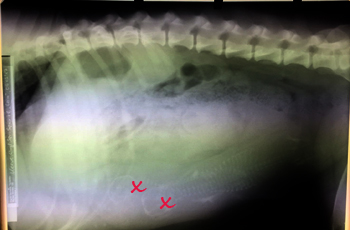

Lara und Pitufo fanden wir dann vor in einem Untersuchungsraum auf einer weichen Matraze und unter einer Rotlichtlampe- Lara am Tropf aber schon recht wach. Als wir kamen wollte sie umgehend mit uns los nach Hause. Die Ärztin die den Kaiserschnitt gemacht hatte klärte mich dann über die OP und die folgenden Risiken einer Gebärmutterentzündung auf. Auslöser des ganzen Dilemmas war nicht der auf dem Röntgenbild gut sichtbare Zwilling gewesen, sondern noch ein dritter Welpe über den erfahrene Züchter auf dem Röntgenbild schon spekuliert hatten. Nur schemenhaft war er auf dem Bild zu sehen, leicht zu übersehen. Er war schon recht lange tot und seine Zersetzung hatte zu der grünen Flüssigkeit in der Gebärmutter geführt.

Zwillinge!

Allen die beim Röntgen mitgefiebert haben ein dickes Dankeschön! Weiterhin brauchen wir alle Daumen, dass die Zwillinge die auf dem Bild erkennbar sind auch frisch und munter in der Wurfkiste ankommen. Wir freuen uns verhalten, dass es doch zwei kleine P´s sind und hoffen und hoffen, dass für beide alles gut geht.